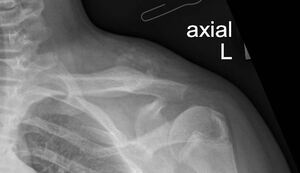

Plain radiography revealed a calcified mass with associated periosteal reaction along the left clavicular shaft (Figure 1). An MRI scan was also done and reported an avidly-enhancing T1w-isointense and T2w-hyperintense lesion in the middle-distal third of the left clavicle, measuring approximately 3.1cm x 2.8cm x 2.3cm (Figure 2). In certain areas, the lesion was inseparable from the adjacent periosteum (Figure 3), which itself was significantly thickened and enhancing. There was also increased T2W marrow edema with enhancement and some adjacent soft tissue swelling. No associated fracture was noted. The MRI report was suggestive of a malignant lesion such as soft tissue sarcoma.

Subsequently, the patient was referred to musculoskeletal oncology given the high suspicion of malignancy. Conservative treatment was adopted for this patient, including a 3 months prescription of Indomethacin and continual radiographic monitoring. Spontaneous resolution of the mass was observed over the next six months, as evidenced by plain radiography (Figure 5). At the fifth month of follow-up, the patient was asymptomatic and exhibited normal function with a full range of motion in the left shoulder. Consequently, the patient was given an open dated review.